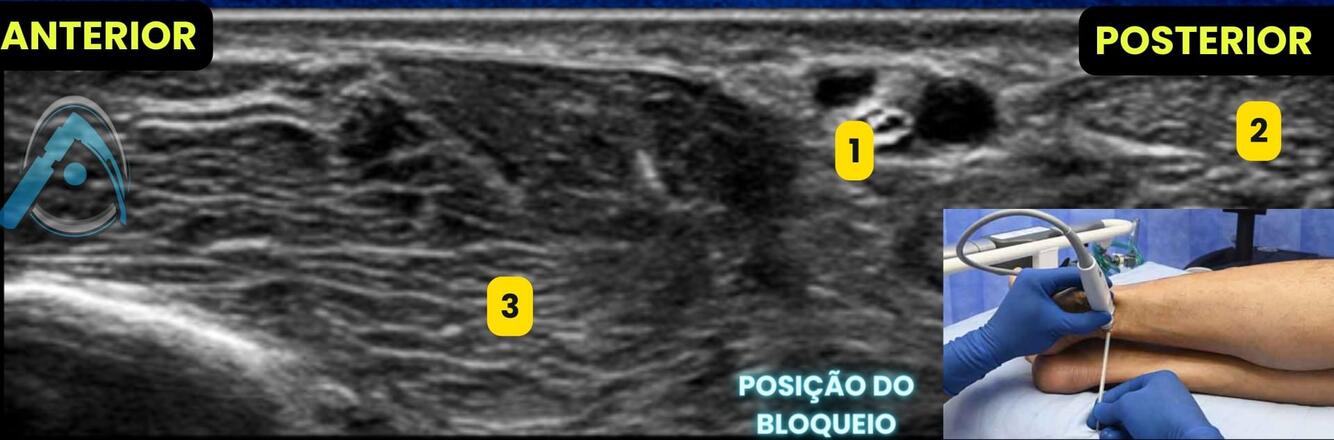

No bloqueio abaixo para uma cirurgia de pé, o que são as estruturas apontadas?

A